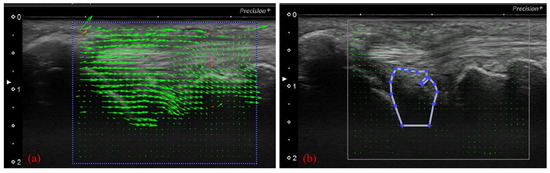

Motion Analysis of Triangular Fibrocartilage Complex by Using Ultrasonography Images: Preliminary Analysis

by Issei Shinohara, Atsuyuki Inui, Yutaka Mifune, Hanako Nishimoto, Kohei Yamaura, Shintaro Mukohara, Tomoya Yoshikawa, Tatsuo Kato, Takahiro Furukawa, Yuichi Hoshino, Takehiko Matsushita and Ryosuke Kuroda

Sensors 2022, 22(1), 345; https://doi.org/10.3390/s22010345 - 4 Jan 2022

The triangular fibrocartilage complex (TFCC) is a significant stabilizer of the distal radioulnar joint. Diagnosing TFCC injury is currently difficult, but ultrasonography (US) has emerged as a low-cost, minimally invasive diagnostic tool. We aimed to quantitatively analyze TFCC by performing motion analysis by [...] Read more.

The triangular fibrocartilage complex (TFCC) is a significant stabilizer of the distal radioulnar joint. Diagnosing TFCC injury is currently difficult, but ultrasonography (US) has emerged as a low-cost, minimally invasive diagnostic tool. We aimed to quantitatively analyze TFCC by performing motion analysis by using US. Twelve healthy volunteers, comprising 24 wrists (control group), and 15 patients with TFCC Palmer type 1B injuries (injury group) participated. The US transducer was positioned between the ulnar styloid process and triquetrum and was tilted ulnarly 30° from the vertical line. The wrist was then actively moved from 10° of radial deviation to 20° of ulnar deviation in a 60-rounds-per-minute rhythm that was paced by a metronome. The articular disc displacement velocity magnitude was analyzed by using particle image velocimetry fluid measurement software. The mean area of the articular discs was larger on ulnar deviation in the control group. The mean articular disc area on radial deviation was larger in the injury group. The average articular disc velocity magnitude for the injury group was significantly higher than that for the control group. The results suggest that patients with TFCC injury lose articular disc cushioning and static stability, and subsequent abnormal motion can be analyzed by using US. Full article